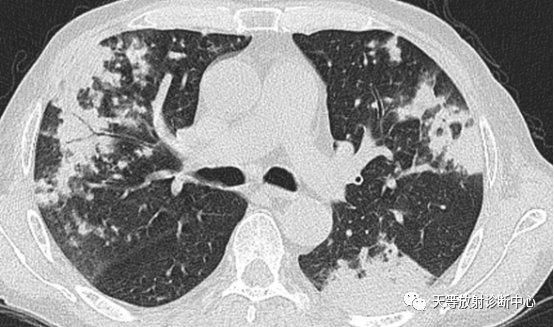

▲右肺大片状实变影,肺炎型肉芽肿组织,肺内播散病灶。

▲两肺大片状实变影,肺炎型结核;